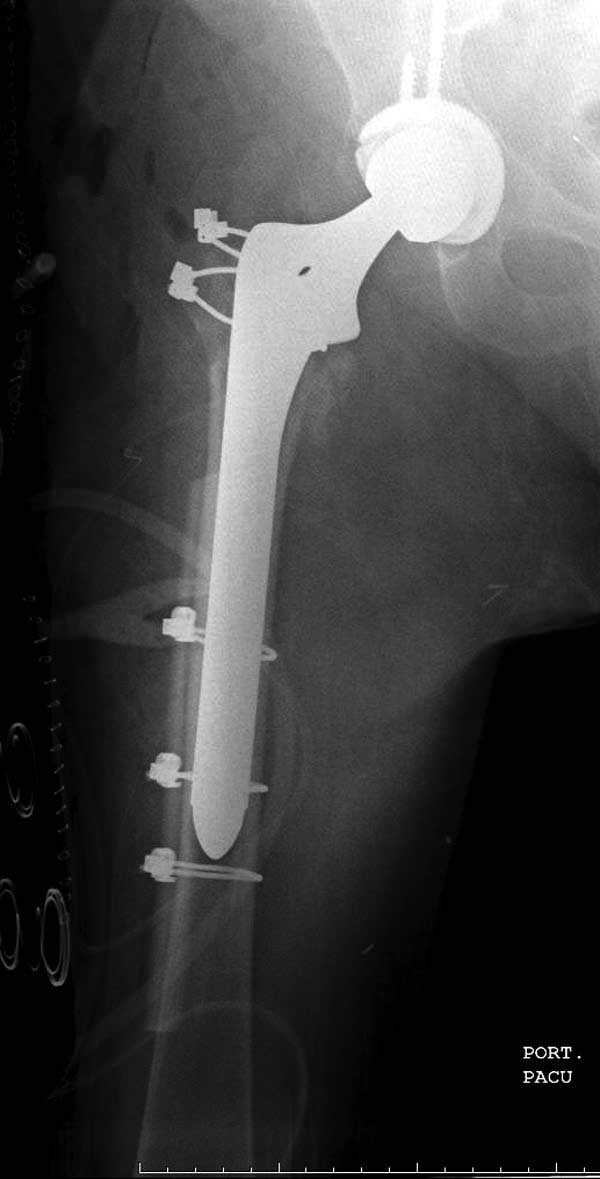

Третья операция-продолжения усилии “синьорами пэрами” по разрушению нормальной анатомии. Крест на головку! По видимому возраст позволяет биполярную конструкции, и при дефекте  calcar пошли на обычный цементный. Ягодичные мышцы потеряли связь с вертелом, т.е. отсутствует верхний удержатель, и результат “a Big Screw Up!” Снимки вызывают головокружение!

Такие “чужие осложнения” встречаются у всех и представляю банальный случай, который шаг за шагом показано как перерос в более сложный процесс... Больная 70 лет, множественные ко-морбидности, чрезвертельный перелом первоначально фиксирован Гамма 3. Осложнение в течение 6 недель, ревизия тотальной артропластикой и во время установки ножки обнаружена трещина диафиза (17), из малого доступа фиксация алло-графтом.